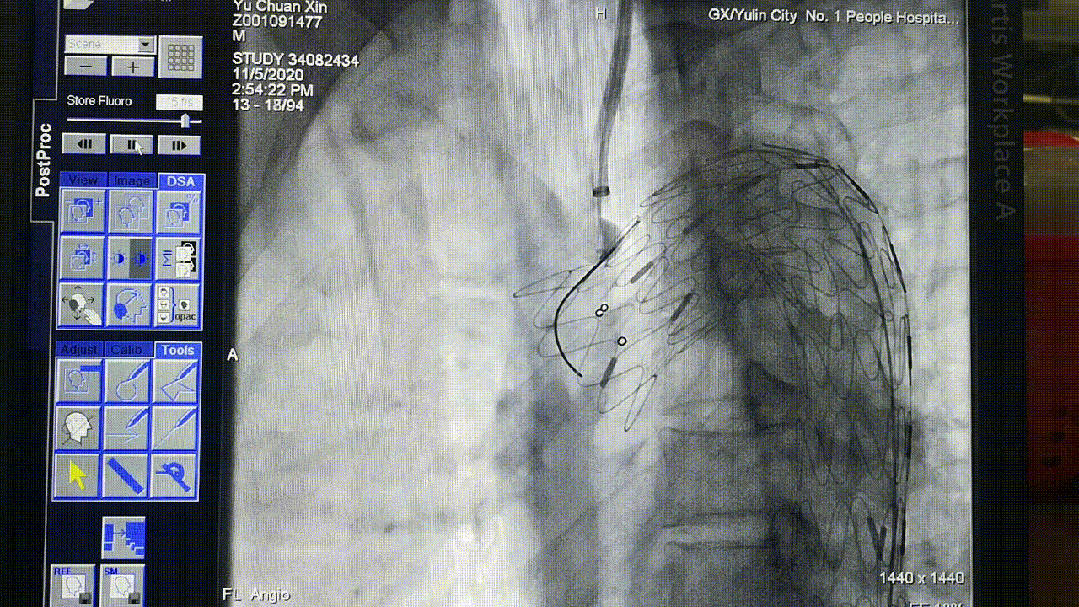

后释放支架预开窗病例

导丝破膜,各角度反复确认